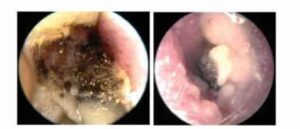

Otomikosis ditandai dengan keluhan nyeri (otalgia), keluar cairan (otorrhea), gangguan pendengaran hingga hilang pendengaran, telinga rasa penuh, gatal dan mendengung (tinitus). Tetapi otomikosis dapat pula tanpa keluhan. Otomikosis yang tidak bergejala dan tidak ditangani berpotensi menyebabkan hilangnya pendengara. Pada pemeriksaan menggunakan otoskop dapat ditemukan pembengkakan (edema), kemerahan (hiperemis) kulit liang telinga luar, pengelupasan epitel superfisial, penumpukan debris yang berbentuk hifa, serta supurasi

Pada tahap awal infeksi, pertumbuhan jamur terlihat sebagai spora berwarna putih atau hitam pada infeksi yang disebabkan Aspergillus spp atau adanya deposit “creamy” atau kental pada infeksi yang disebabkan oleh Candida spp.